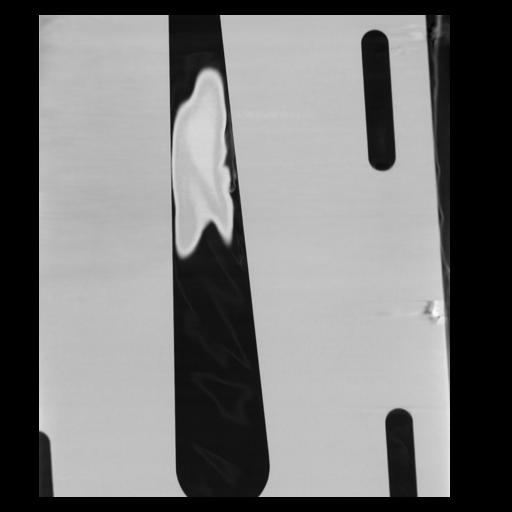

29 CUERPO,CE,Coronal,3.000,CUERPO,Coronal,